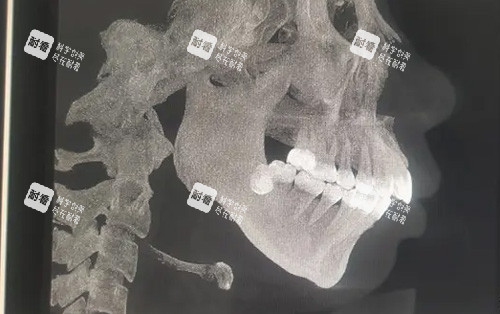

颌面手术是“在骨头上绣花”,稍有不慎就可能伤到神经、血管,导致面瘫、牙齿松动。万启龙用“计算机辅助设计+3D打印导板”,术前模拟手术过程,术中用导板定位,把骨头移动的误差控制在0.5毫米内,确保术后咬合稳、面部对称。

万启龙的方案是“精细打击”:术前正畸8个月,用直丝弓矫治器调整牙齿轴向;术中采用“单侧下颌矢状劈开术”,只切割左边下颌骨,把它往后移3毫米,同时用3D打印导板辅助定位,确保骨头移动“不偏不倚”;术后正畸4个月,关闭剩余间隙。